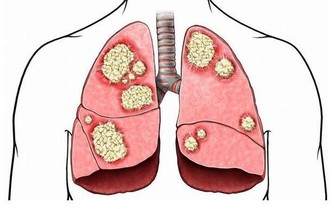

危害五:誘發癌症。

便秘的人,毒素持續刺激腸粘膜,會誘發腸癌發生。